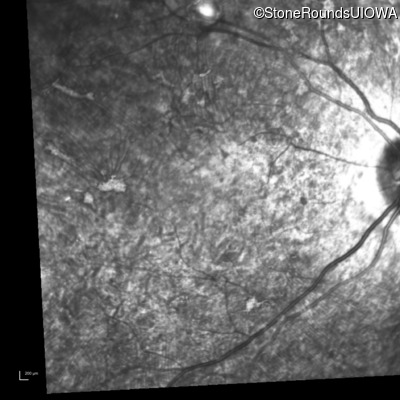

Infrared Fundus Photograph - Left - 20/400 sc

Exemplar